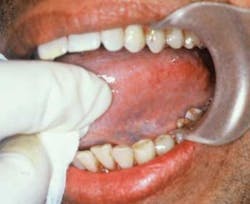

Your patient today is a 57-year-old male, Deepak. The new patient appointment (90 minutes) follows your usual protocol of a patient exam and treatment plan, radiographs, a thorough medical history, and prophylaxis. During the conversation with Deepak, you notice that his teeth are stained and they appear somewhat worn. During the exam, you also notice discoloration of the tissue in the vestibule especially, and you observe further white thick striations within the tissue. Recession is noted throughout. The tissue appears smooth and the striations appear to be intrinsic rather than extrinsic.

Figure 1: Submucous fibrosis noted with white striations.

You begin to search the possibilities for these observations and the etiology. As you question Deepak, you find that he has used areca nut and practiced betel nut chewing throughout his life. In this case, what you are observing is oral submucous fibrosis (SMF) resulting from chronic use of these products (Figure 1).

The use of such products stimulates the production of collagen by fibroblasts, and chronic use of the substances causes a cross-linking of the newly formed fibers. The body cannot break these down and they continue to strengthen. The white striations that are visible clinically denote what is happening microscopically. The tissue goes through several stages of progression to the premalignant state of submucous fibrosis.

Stage 1: Generalized stomatitis – This stage may present with ulcers, erythema, and vesicles. Because of the pigmentation of the areca nut, the teeth become stained, and the staining usually promotes questioning by the dental professional in trying to determine the etiology.

Stage 2: Fibrosis – The accumulations of fibrous bands are noted within the collagen. A white striation is also noted clinically. The deeper tissues are affected and eventually the muscles of the oral cavity tighten. The fibrosis makes the mouth restricted and continues to tighten as the tissue changes progress. Movement of the tongue is restricted and speech may be affected. Over time, the lips, soft palate, esophagus, and the oropharynx are affected as well.

Stage 3: The SMF is classified as premalignant leukoplakia-type lesions.